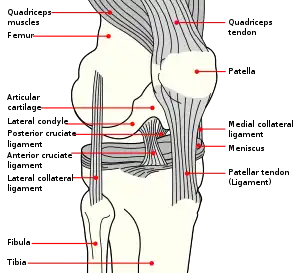

Anatomy of the knee

The patella is a triangular sesamoid bone which is embedded in tendon. It rests in the patellofemoral groove, an articular cartilage-lined hollow at the end of the thigh bone (femur) where the thigh bone meets the shin bone (tibia). Several ligaments and tendons hold the patella in place and allow it to move up and down the patellofemoral groove when the leg bends. The top of the patella attaches to the quadriceps muscle via the quadriceps tendon,[2] the middle to the vastus medialis obliquus and vastus lateralis muscles, and the bottom to the head of the tibia (tibial tuberosity) via the patellar tendon, which is a continuation of the quadriceps femoris tendon.[13] The medial patellofemoral ligament attaches horizontally in the inner knee to the adductor magnus tendon and is the structure most often damaged during a patellar dislocation. Finally, the lateral collateral ligament and the medial collateral ligament stabilize the patella on either side.[2] Any of these structures can sustain damage during a patellar dislocation.